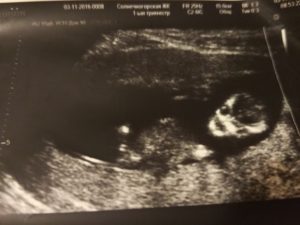

Пол ребенка в 11 недель по узи

Фото снимок плода на 11 неделе

УЗИ на 11-й неделе беременности.Скрининг 11 недельУЗИ на 11-й неделе беременности.Скрининг 11 недель

К моменту первого посещения УЗИ рост ребенка, вернее, копчико-теменной размер, равен 4-5 сантиметрам. У ребенка сформировались уже необходимые органы, их можно рассмотреть на экране монитора. Правда, ручки и ножки у него еще непропорционально сложены. А ручки даже длиннее ножек, зато они уже хватают вокруг. Малютка уже активен.

Есть уже и камеры в сердечке. Пульс ударов 120-160 в минуту. Но еще нет различий между венозным и артериальным потоками.